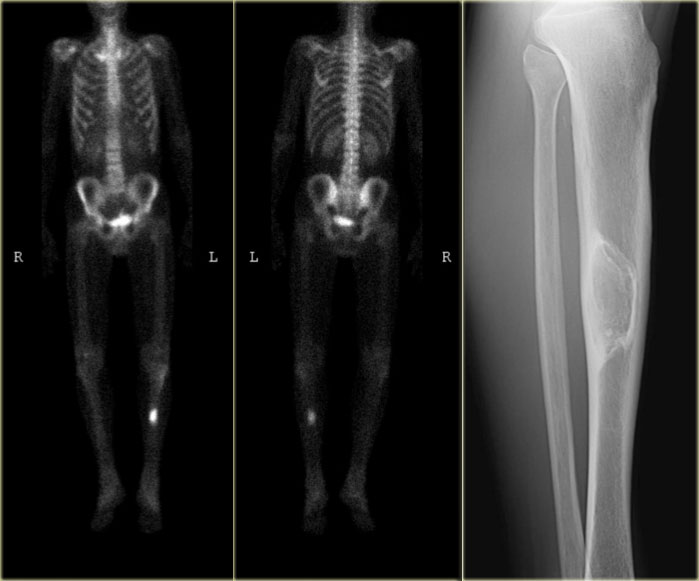

Low grade chondrosarcoma: Bone scintigraphy (left) and fast dynamic contrast enhanced MR (right) Low grade chondrosarcoma: Bone scintigraphy (left) and fast dynamic contrast enhanced MR (right)

Bone scintigraphy of the same patient shows increased uptake in the lesion.

This increased uptake in a chondroid tumor is in favor of the diagnosis of a low grade (grade I) chondrosarcoma.

The fast dynamic contrast enhanced MR image with subtraction revealed early and progressive enhancement, which is also in favor of the diagnosis of a grade I chondrosarcoma.